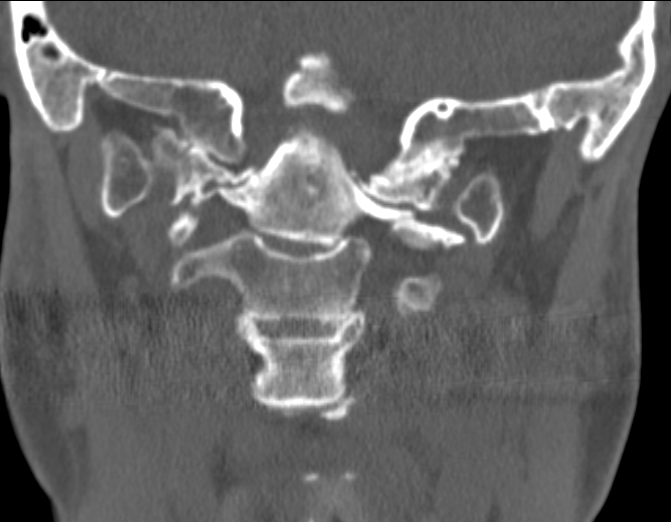

1. CT of CVJ. Left: coronal CT shows severely upslanting and elevated left occipital condyle–C1 joint (arrows). C4 is a hemi-vertebra. Right: sagittal CT shows invagination of the opisthion (Op) (basilar invagination). The posterior arch of C1 is assimilated into the posterior rim of the foramen magnum. Note slightly high-riding odontoid but absence of platybasia, short clivus or retroflexed dens.